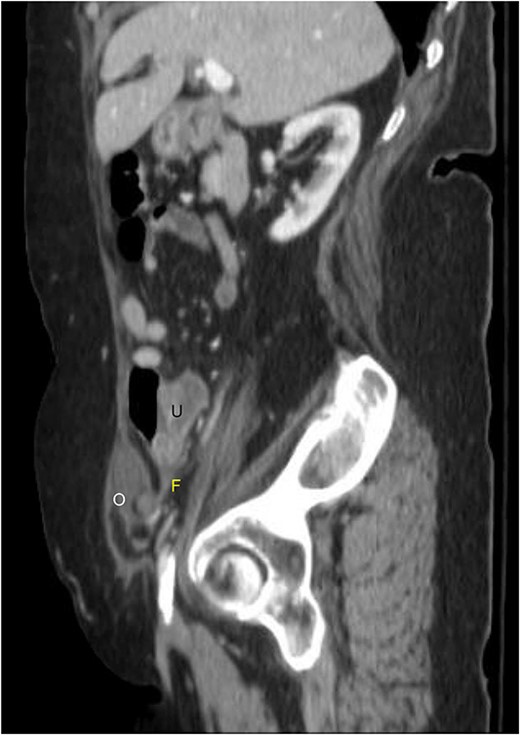

A 76-year-old Caucasian female presented to the emergency department for evaluation of 3 days of progressively worsening abdominal pain. The pain was characterized as an ache, originated in the right lower quadrant and radiated to the bilateral upper quadrants. Past medical history was significant for obesity (BMI 31 kg/m2), chronic obstructive pulmonary disease, gastroesophageal reflux disease, hypertension, hypothyroidism, heart failure with preserved ejection fraction, atrial fibrillation, and scleroderma. Pertinent surgical history included a dual-chamber pacemaker and tubal ligation. She was anticoagulated with apixaban. Physical examination revealed right lower quadrant tenderness to palpation and rebound tenderness without a palpable abdominal bulge. Contrast-enhanced computed tomography of the abdomen and pelvis did not clearly demonstrate the appendix, but rather a ventral hernia in the lower right quadrant. The fascial defect was lateral to the rectus abdominis, superior to the inguinal ligament, and inferior to the arcuate line. The defect measured 3.6 × 2.0 cm and involved the transversus abdominis and internal oblique muscle aponeuroses while the external oblique remained intact, consistent with Spigelian hernia (Fig. 1). There was an oblong structure extending parauterine into the hernia sac with a small amount of free fluid suggestive of the right ovary and fallopian tube (Fig. 2). Considering these findings and appropriate cessation of anticoagulation, the patient was taken for diagnostic laparoscopy and transabdominal preperitoneal hernia repair.

Sagittal view of contrast-enhanced computed tomography of the abdomen and pelvis demonstrating the right fallopian tube (F) attached to the uterus (U) extending into the Spigelian hernia defect containing the right ovary (O).